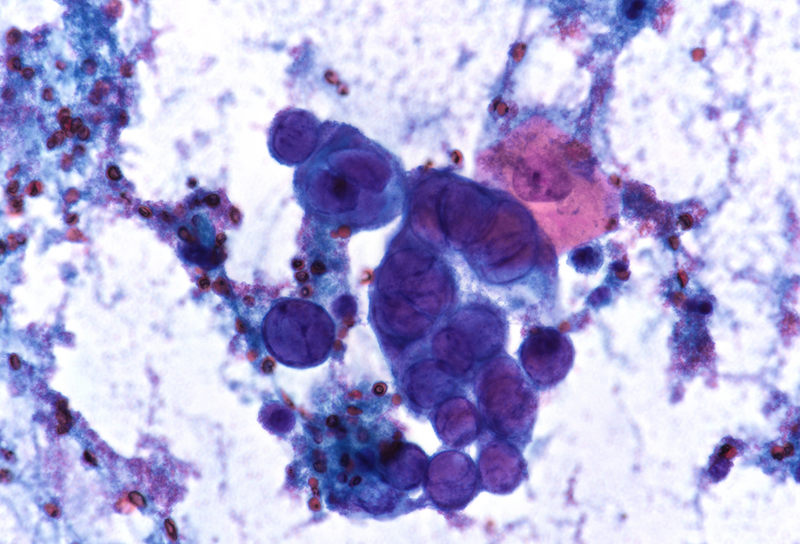

Cytology disclosed groups of squamous cells with enlarged ground-glass nuclei with homogenous chromatin pattern and multinucleation (Panels C-D). Upon histology, we observed multiple fragments of squamous epithelium with degenerating features admixed with inflammatory detritus. The nuclei of the squamous cells displayed ground-glass morphology as documented in the cytological material (Panels E-F). Immunostaining for Herpes simplex virus (HSV) I and II was positive (Panels G-H).

Histologically, the virus infects oesophageal squamous epithelium, typically at the superficial lateral margin of ulcers and erosions. The morphological diagnostic criteria include: (i) dense intranuclear eosinophilic to amphophilic round inclusion bodies with a clear halo separated from the nuclear membrane (Cowdry A inclusions), (ii) ground-glass nuclei with homogenous chromatin pattern, (iii) nuclear molding, (iv) multinucleated syncytia giant cells and (v) detached ballooning degeneration of infected cells. Immunohistochemistry studies is helpful in equivocal cases.